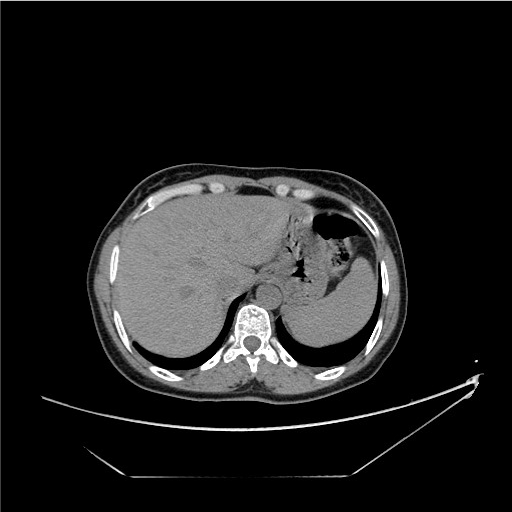

Figure 2: Abdominal computed tomography scan after 6 cycles of chemotherapy.